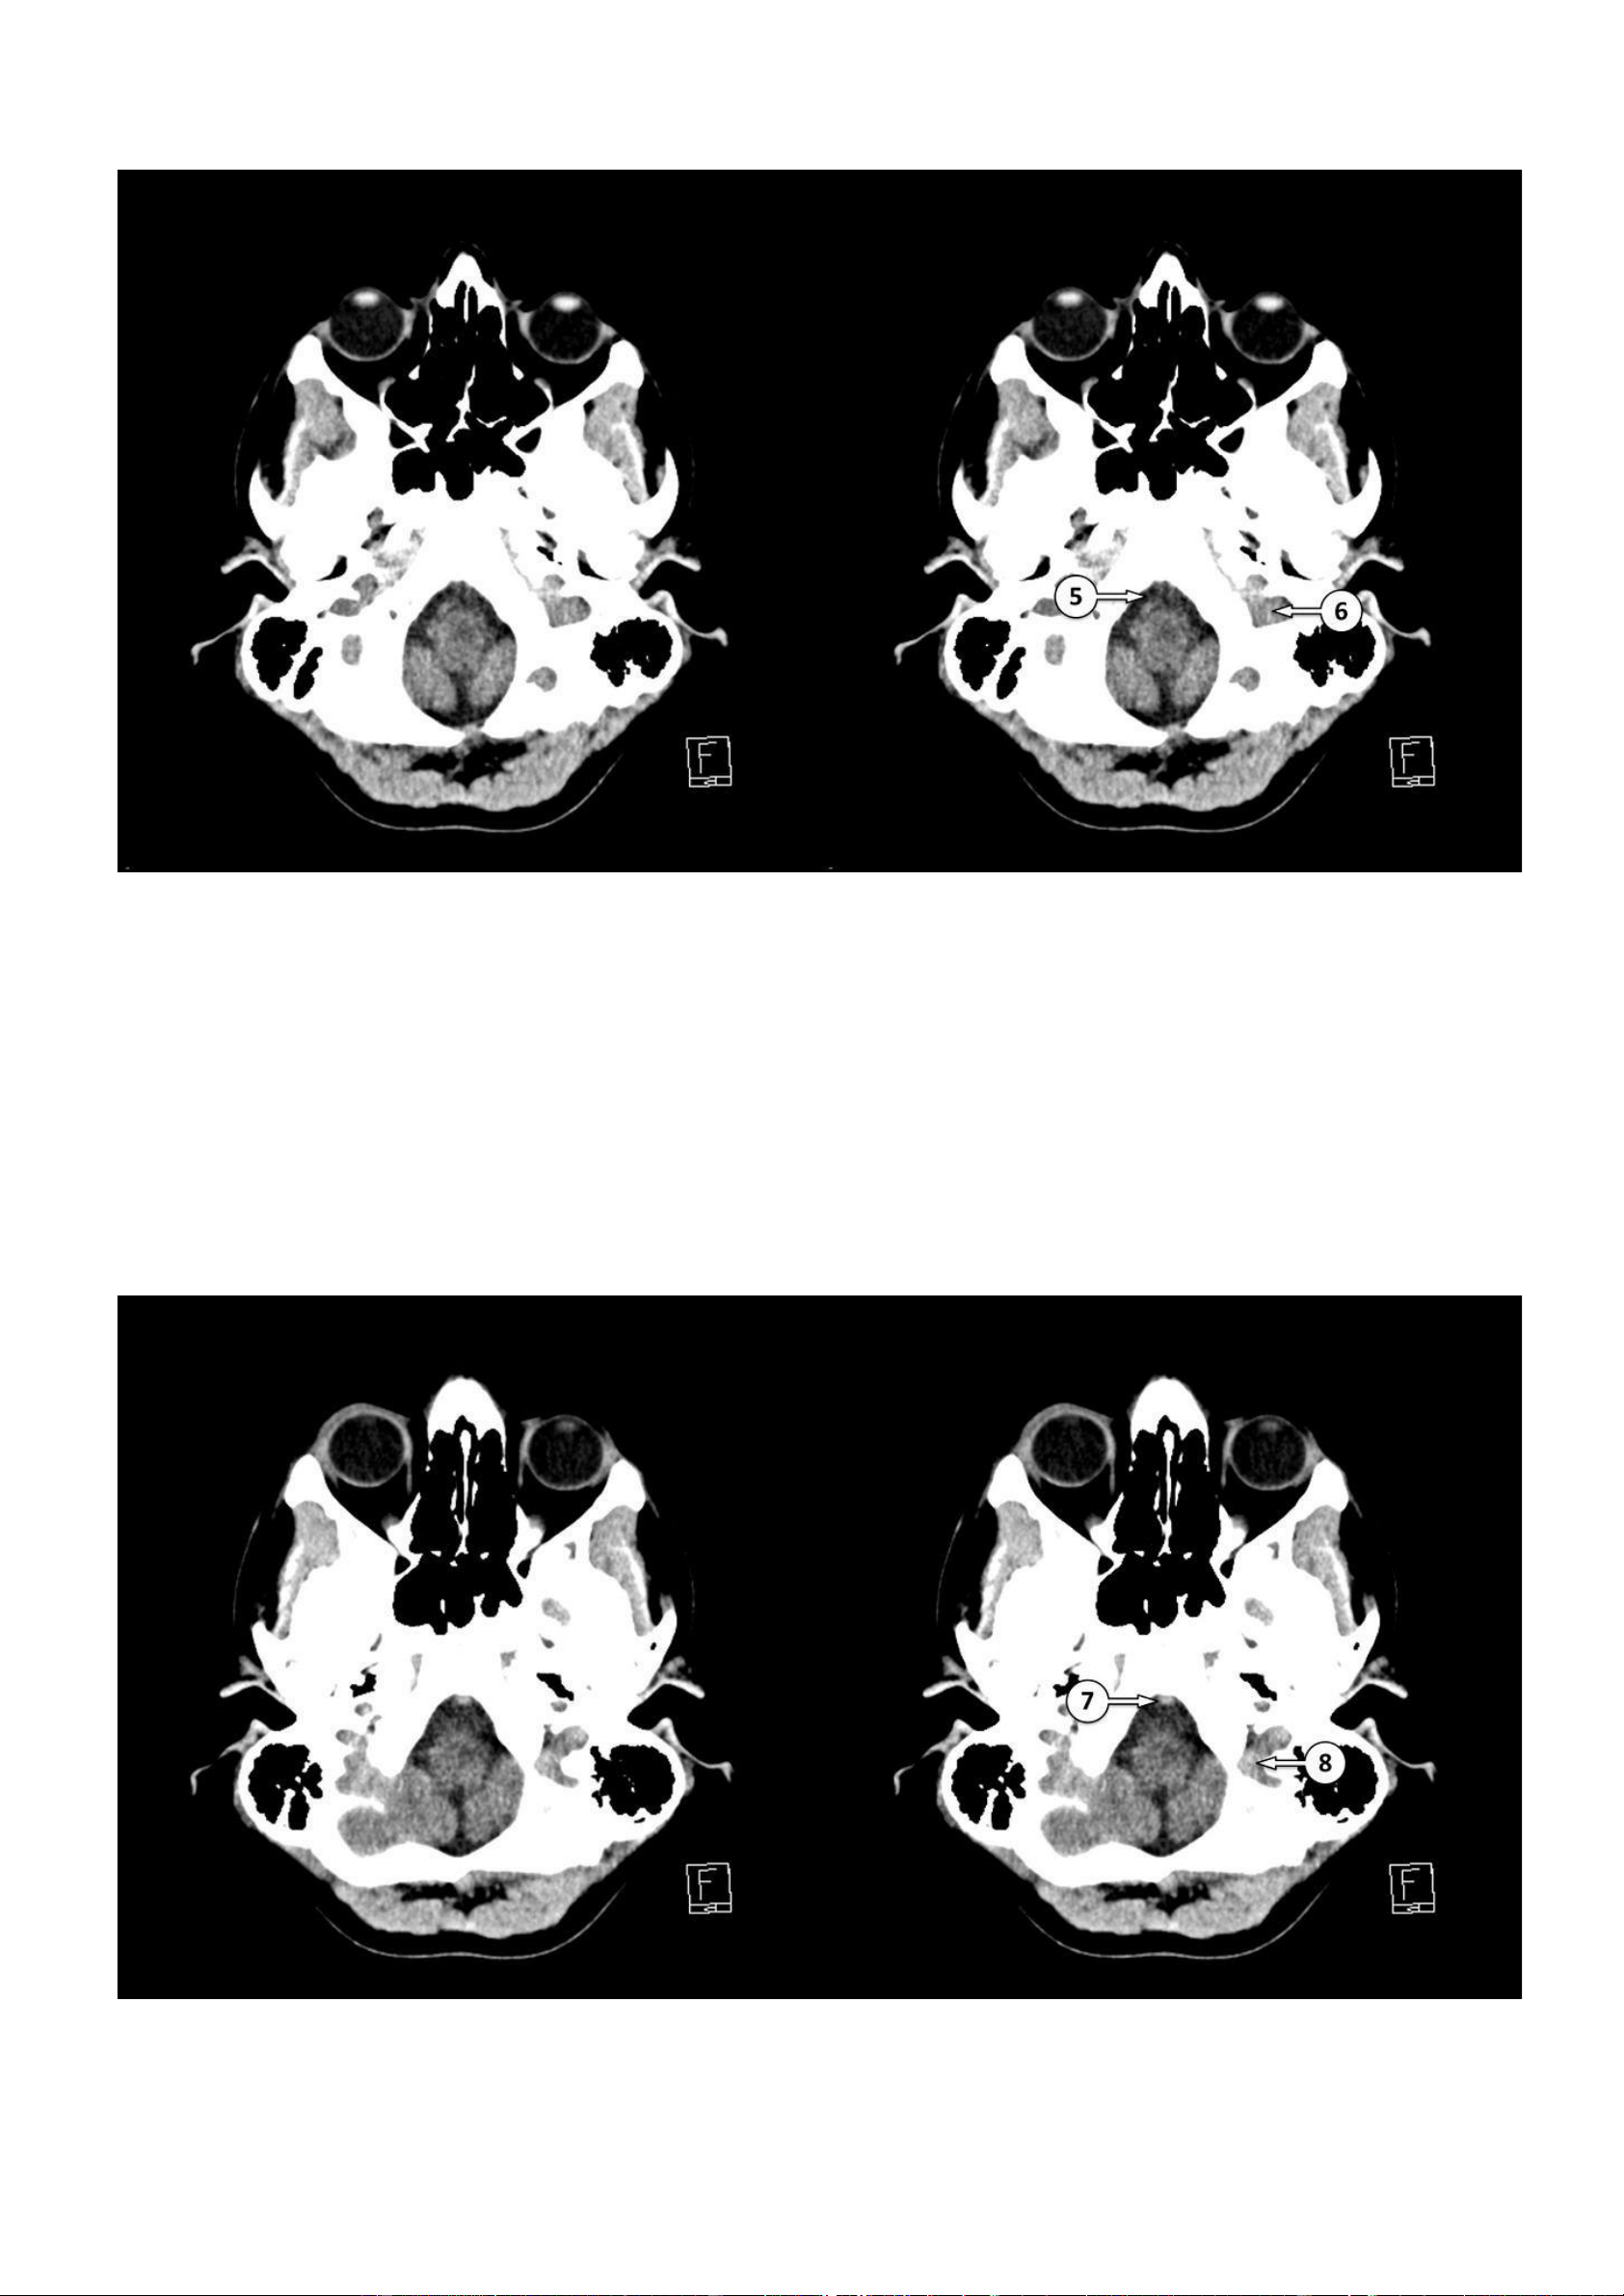

▪ Số 5: Bể trước hành não

▪ Số 6: Tĩnh mạch cảnh trong 7: Động mạch thân nền 8: Xoang xích-ma lOMoAR cPSD| 22014077